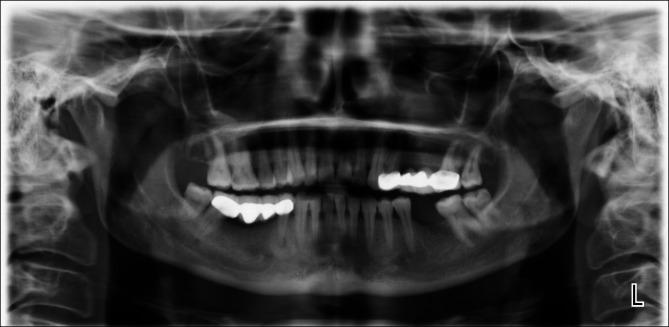

Rheumatoid arthritis (RA) and ankylosing spondylitis (AS) have different effects on bones, cartilage and joints, sometimes destroying the spine and joints, and other times causing new bone formation. This study aimed to evaluate the effects of RA and AS on the types (radiolucent, radiopaque and mixed) of periapical lesions in jaw bones.

METHODS

This study included 708 individuals (97 with AS, 327 with RA and 284 healthy controls (C)) and a total of 17,118 teeth (AS: 2,442; RA: 7,638; C: 7,038). The number of teeth, extracted teeth and teeth with root canal treatment and the presence of radiopaque, radiolucent and mixed periapical lesions were recorded from dental panoramic radiographs. Kruskal-Wallis and chi-square tests were used for statistical analysis.

RESULTS

The frequency of radiopaque lesions in the AS and RA groups was similar (p > 0.05) and significantly higher than in the C group (p < 0.05) (AS: 13.4%; RA: 6.1%; C: 2%). Mixed lesions (AS: 3.1%; RA: 4.0%; C: 0.4%) were statistically significantly higher for the RA group compared to the C group (p < 0.05), while the AS-C and AS-RA groups were similar (p > 0.05). There was no significant difference in terms of radiolucent lesions among groups (p > 0.05).

CONCLUSION

Radiopaque apical lesions were frequent in RA and AS patients, while mixed lesions were significantly higher in RA patients.